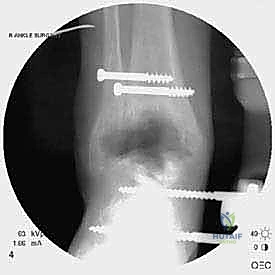

من أعقد التحديات التي تواجه جراحي العظام هي حدوث كسور في الكعب الداخلي (Medial Malleolus) أو الخارجي (Lateral Malleolus) في وجود مفصل صناعي. تحدث هذه الكسور لعدة أسباب:

1. ترقق العظام: حول المفصل الصناعي نتيجة لعدم استخدام الطرف بشكل طبيعي (Stress Shielding).

2. الاصطدام الميكانيكي (Impingement): إذا كان حجم المفصل الصناعي أكبر من اللازم، فقد يضغط على الكعبين من الداخل ويؤدي لكسرهما بمرور الوقت.

3. الإصابات المباشرة: مثل السقوط أو التواء الكاحل.

علاج هذه الكسور يتطلب مهارة فائقة من الدكتور محمد هطيف، حيث يتم استخدام تقنيات الجراحة الميكروسكوبية وتثبيت الكسور باستخدام صفائح معدنية دقيقة ومسامير (Locking Plates) دون المساس بثبات المفصل الصناعي، أو يتم دمج علاج الكسر ضمن عملية مراجعة المفصل الكلية إذا كان المفصل نفسه تالفاً.